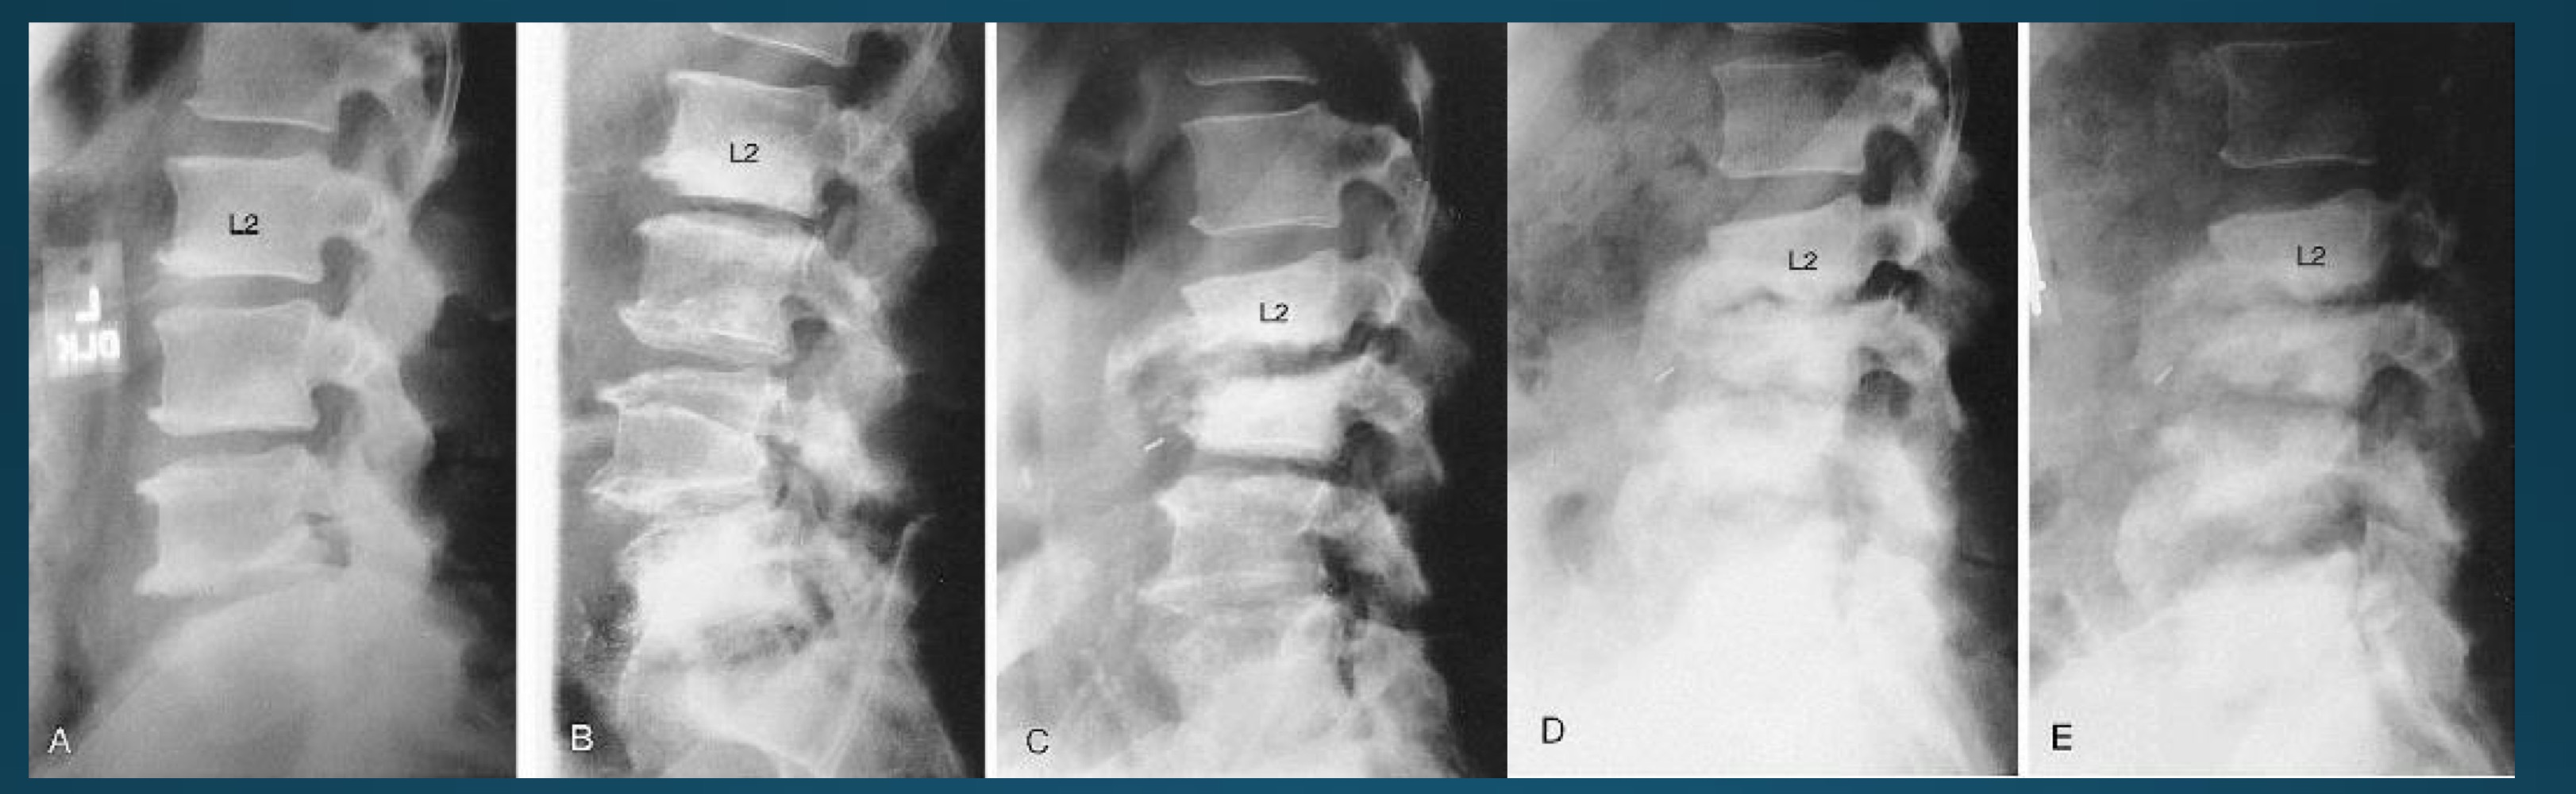

what are the signs seen in this image? what diagnosis would you make?

barrel shaped vertebra

AS

what type of seronegative arthritis is marked by marginal syndesmophytes?

what is the difference between AS and DISH ossification between vertebra

facet joints are ankylosed in AS

appearance of spine in AS AKA

bamboo spine

what do you call this sign? what diangosis is this apart of?

trolley track sign

dagger sign

andersson lesion